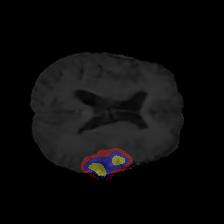

Brain tumor segmentation. Segmenting tumors in brain is challenging due to the high variance in appearance and shape of the tumors [28]. We use a subset of the 2017 Brain Tumour Image Segmentation (BraTS) dataset [29, 26]. It contains multi-parametric 3D MRI scans. The segmentation masks include (possibly overlapping) three classes of tumor. The 3D scans are split into 2D image slices, and only images that contain at least one tumor class are retained. Figure 7 shows three MSGNet generated samples as well as the corresponding masks. Since MSGNet adheres to the underlying relationships between various classes, we see that the generated images and the masks for different tumor classes are in line with the images and masks from the training set. In general, MSGNet rarely generated erroneous samples; we found roughly one sample per 3000 generations that could be rejected. Similar to the malaria experiment, we observed an improvement of 3.1% () in -score on the validation set.

A subset of the BrATS dataset was used. We used the images accompanied by segmentation layouts from the FLAIR and T1Gd modes. The segmentation layouts showed the sub-regions for three different classes: GD-enhancing tumor, the peritumoral edema, and the necrotic and non-enhancing tumor core. The brain and the background were treated as an additional class. We refer to [32] for further details. For the two modes, the background has been modelled using two different classes. We only considered half of the 155 slices, i.e., we took only the even-numbered slices and out of those we discarded the slices that did not include one of the previously mentioned tumor-classes in order to create a more balanced dataset. This resulted in 20,000 images that were further augmented with 6,000 MSGNet generated images. Example generations of the masks as well as the images are shown in Figure 12.